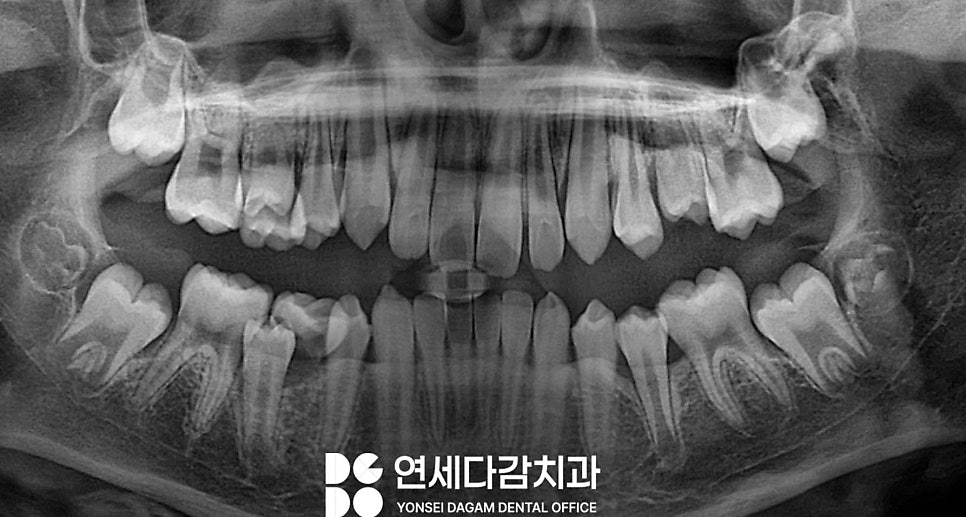

엑스레이를 통한 검진을 통해

영구치가 정상적인 맹출 양상을 보이고

있는지 확인하는 것이 안전합니다.

가락시장역 치과에서는

정기 검진 때마다

파노라마 방사선 사진 분석을 통해

발육 상태와 맹출 방향을

확인하여 검진합니다.